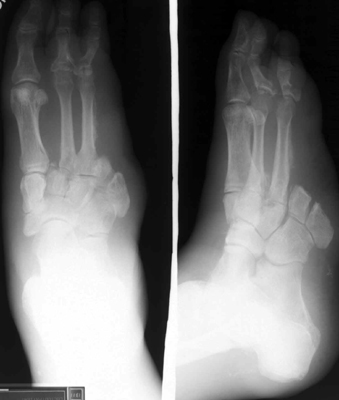

The images to the left show a proximal

transmetatarsal amputation through digits 4 and 5.